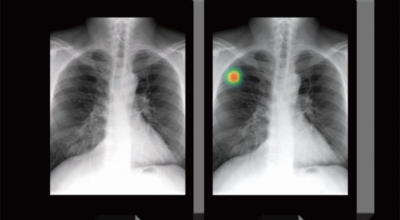

폐암 검사는 X-ray를 통해서 검사하는데 , 크기가 작거나 구석에 위치한 경우 확인이 어려운 경우도 있습니다. 그리고 조직 검사를 통해서 정확한 진단을 하게 돼요. 폐암이 발견되면 종양의 크기나 전이 여부 , 위치에 따라서 수술 여부를 결정하게 돼요.